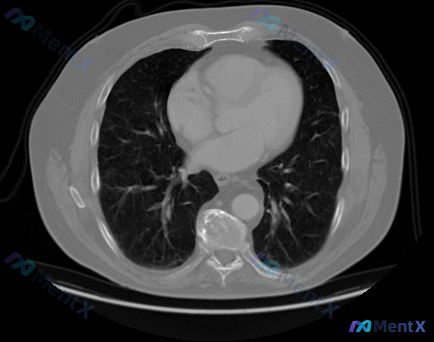

看到一份胸部CT肺窗的横断面图像,一开始觉得肺里挺干净的,但仔细看下去发现了一个非常重要的「红旗征象」,整理了一下完整的分析思路和大家分享。 --- 先看完整的影像表现 1. 肺实质与气道:双肺纹理走行大致正常,未见明显实变影、大片磨玻璃影,也没有看到明确的结节或肿块影;气管及双侧支气管主干腔径清晰...